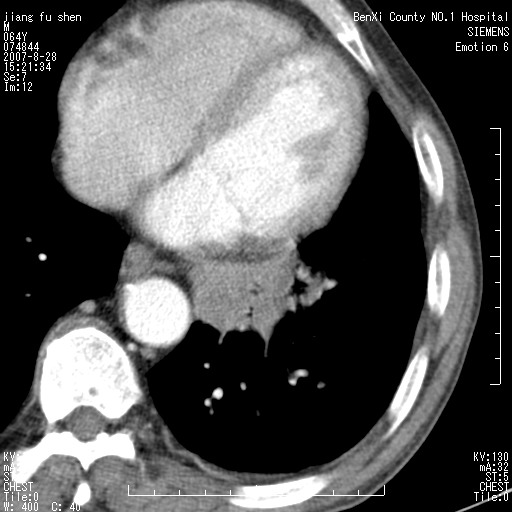

男、64、咳嗽、发烧一周、左肺呼吸音稍弱。既往肺结核,右手结核。

本次扫描患者未带原片,左肺下叶发现病灶。左肺上叶空洞,5组淋巴结肿大,1cm左右。

左肺下叶前内基底段支气管明显偏心性狭窄,周围分叶状肿块,伴有阻塞性肺炎,支持肺癌可能性大。

考虑左肺中央型肺癌并阻塞性肺炎

支持左侧中央型肺癌伴阻塞性肺炎

左肺下叶中央型肺癌

支持 左下中央型肺癌可能性大。